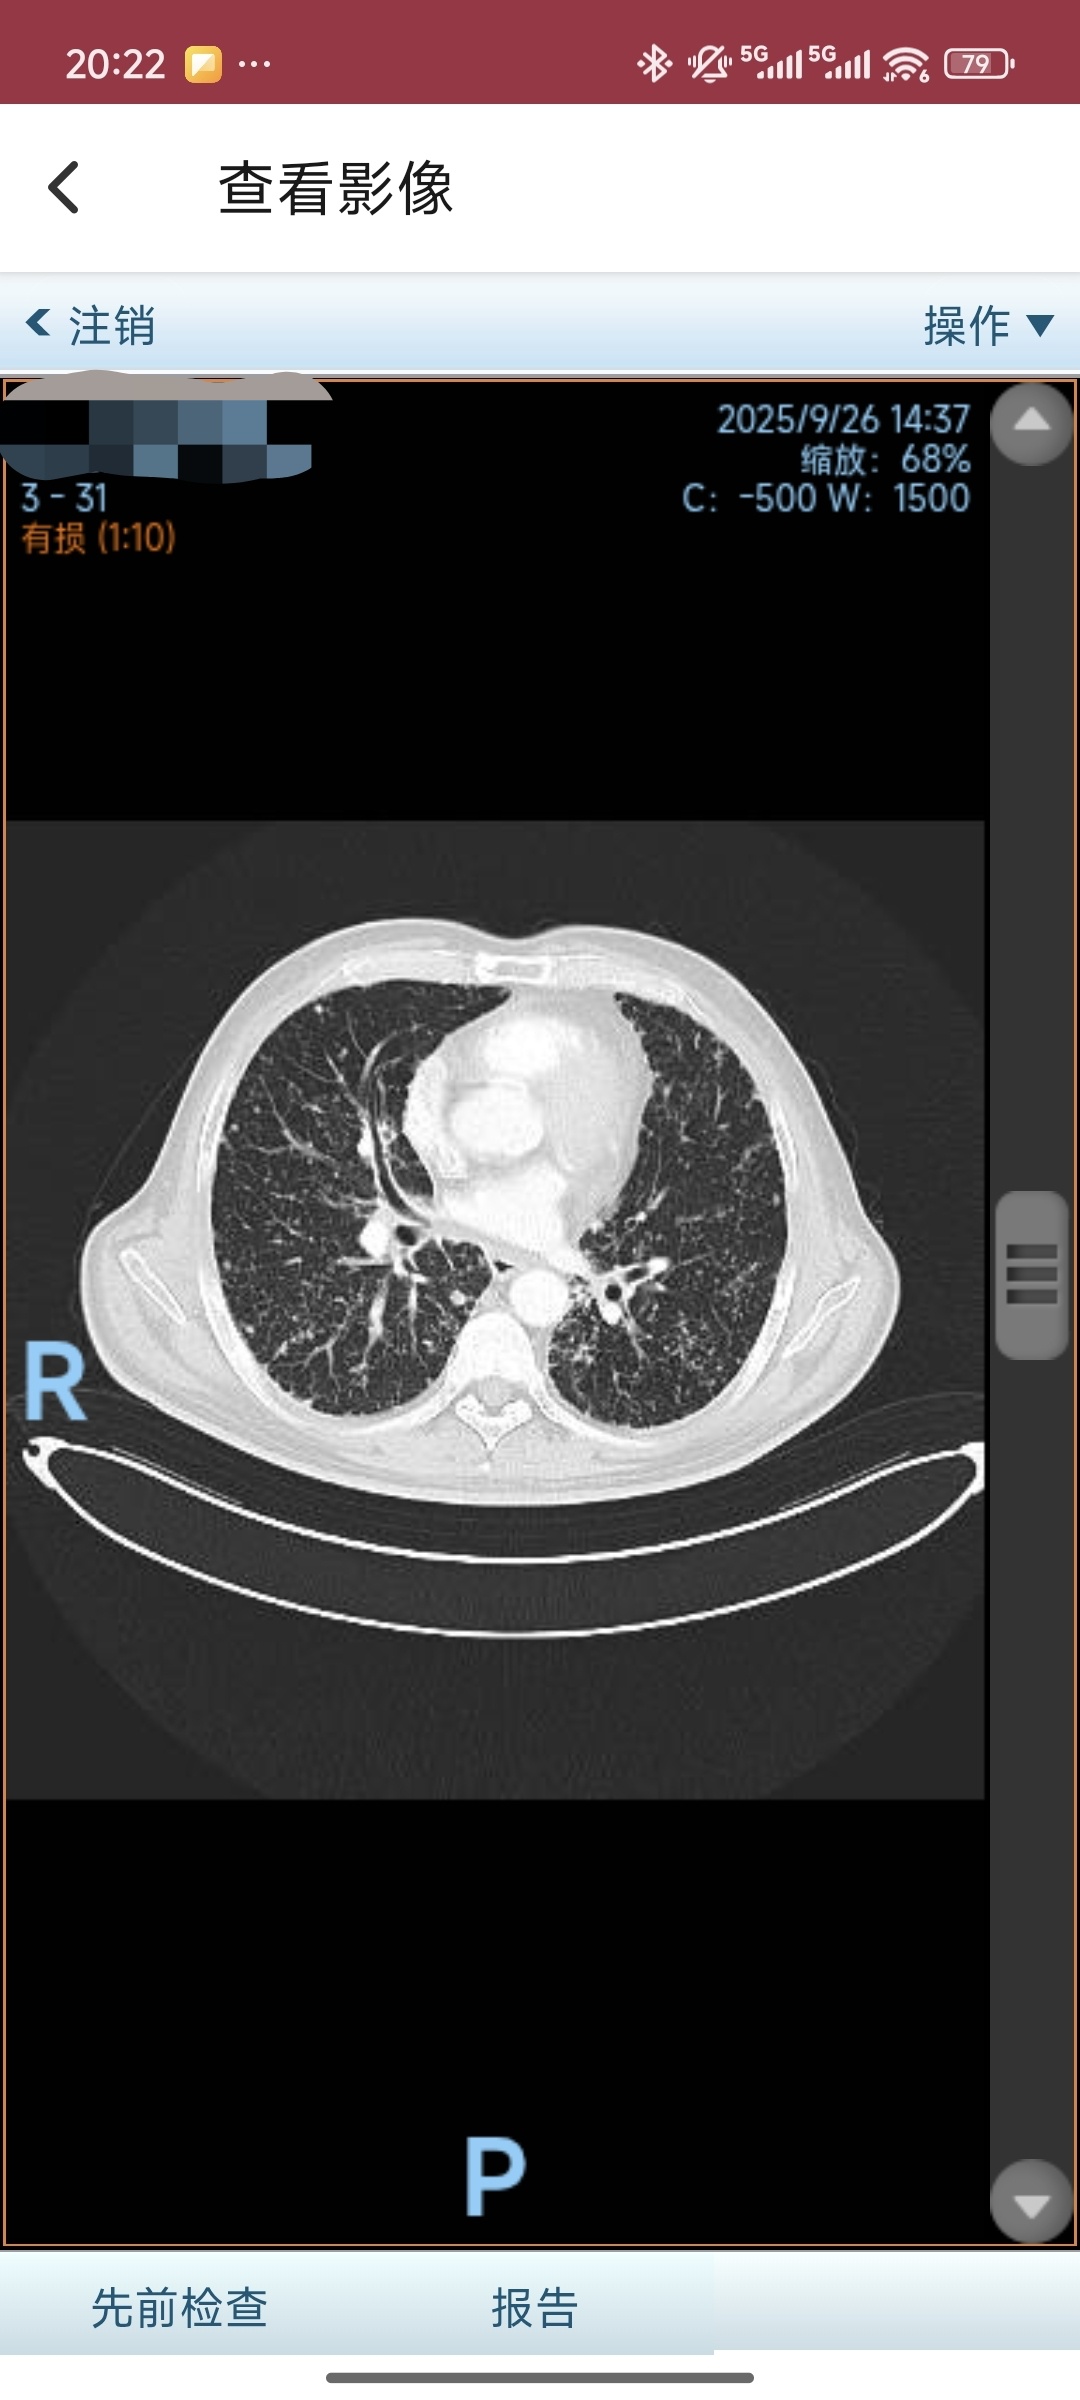

2025-09-26 本院复查胸部CT:左下肺癌缩小,远端肺阻塞性炎症同前;双肺癌性淋巴管炎伴多发转移部分缩小;纵隔、双肺门、锁骨上区

及胸肌间多发淋巴结缩小;少量心包积液同前;多发骨转移同前。